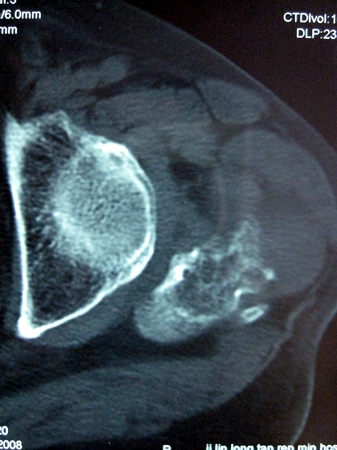

以下是引用lkc8963在2008-12-19 21:19:00的发言:[br]左?右?患侧大转子上移,股骨颈骨质浓杂,髋周见多发条片状骨化影,以小转子为著,多为陈旧性股骨颈骨折后改变并骨化性肌炎.请咨询既往史!